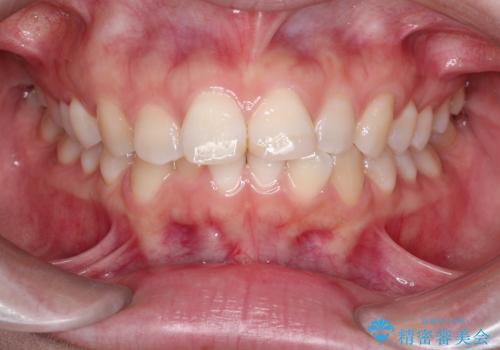

- 前歯のデコボコ(叢生)を気にされてご来院されました。精密な検査の結果、歯が並ぶスペースが不足していることが判明。患者様のご希望から、透明で目立ちにくいインビザライン(マウスピース矯正)による治療計画を立案しました。抜歯を避け、奥歯全体を奥へ動かす遠心移動という方法でスペースを確保し、前歯の叢生を解消することを目指します。

今回の矯正治療では、透明なマウスピース型の装置インビザラインを使用しました。この装置は取り外し可能で、日常生活で目立ちません。治療は、緻密に計算された計画に基づき、段階的に作製されたマウスピースを交換していくことで、奥歯から順に全体を後方へ移動させる遠心移動を実施。これにより、前歯を並べるための十分なスペースが確保され、デコボコが解消されました。抜歯することなく、機能的にも審美的にも整った美しい歯並びを獲得していただけました。